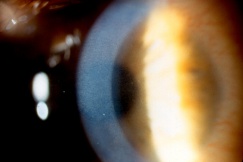

Detachment of the iris root from its insertion site at the ciliary body results in iridodialysis. It frequently occurs after blunt trauma and results in a central D-shaped pupil with a peripheral dark binconvex area where the iris has detached. Associated findings include hyphema, angle recession and peripheral anterior synechiae, and patients can develop chronic open or closed-angle glaucoma. Traumatic aniridia, or complete loss of the iris tissue, can also occur and is usually accompanied by severe intraocular hemorrhage or globe rupture. Aniridia rarely occurs after blunt trauma, but has been reported in eyes that have previously undergone cataract extraction, with the iris exiting a temporarily reopened surgical wound.[30] The iris disinsertion may also be visible in the anterior chamber angle by gonioscopy.

Treatment of iris injury is largely dependent on the severity of glare, diplopia, and decreased visual acuity. Occasionally, unacceptable cosmetic appearance may also be an indication for treatment. Medical management includes the use of miotics and colored contact lenses. Surgical repair of the iris is indicated when a significant visual disturbance is not correctable with medical management alone, when iris diaphragm support is needed for IOL placement, and rarely, for cosmetic reasons. The FDA approved first silicone prosthetic implantable iris device in 2018 (CustomFlex Artificial Iris, HumanOptics) [31]